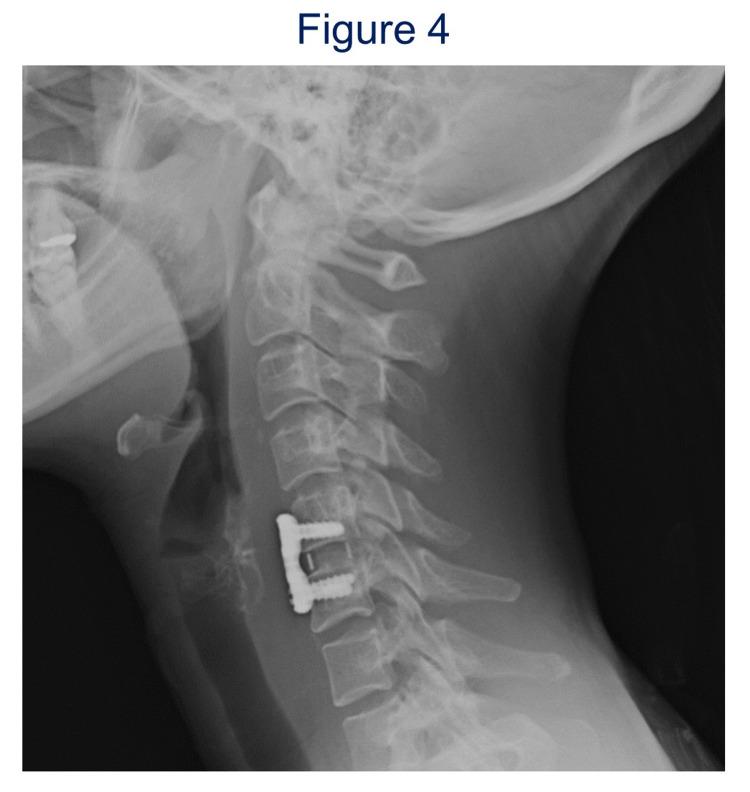

Horner's syndrome is caused by impairment of the sympathetic trunk, resulting in associated ptosis, miosis, and anhidrosis. The cervical sympathetic trunk is sometimes damaged during an anterior approach to the lower cervical spine. We report two cases of Horner's syndrome after anterior decompression and fusion for lower cervical spine pathologies. Case 1 was in a 58-year-old woman with a herniated C5-6 intervertebral disc presenting myelopathy who underwent anterior cervical discectomy and fusion of C5-6. After the operation, miosis and anhidrosis of the right face occurred, and the symptoms continued for more than 15 years. Case 2 was in a 40-year-old woman whose diagnosis was flexion myelopathy with kyphosis at C5-6 and canal stenosis, so she underwent anterior cervical C5-6 discectomy and fusion of C5-6. Immediately after surgery, ptosis and miosis occurred, which lasted for four months. Horner's syndrome tends to occur during anterior cervical spine procedures, especially at the lower level, and the syndrome may be transient or irreversible. During an anterior approach to the lower cervical spine, taking care not to damage the sympathetic trunk is important to avoid this complication.

霍纳综合征由交感神经干受损引起,导致患侧上睑下垂、瞳孔缩小和无汗。在下颈椎前路手术过程中,颈交感神经干有时会受到损伤。我们报告两例因下颈椎病变行前路减压融合术后出现霍纳综合征的病例。病例1为一名58岁女性,患有C5-6椎间盘突出伴脊髓病,接受了颈椎前路椎间盘切除及C5-6融合术。术后,右侧面部出现瞳孔缩小和无汗,症状持续超过15年。病例2为一名40岁女性,诊断为C5-6节段后凸畸形伴椎管狭窄的屈曲型脊髓病,因此接受了颈椎前路C5-6椎间盘切除及C5-6融合术。术后立即出现上睑下垂和瞳孔缩小,持续了四个月。霍纳综合征在下颈椎前路手术过程中容易发生,尤其是在较低节段,该综合征可能是短暂的或不可逆的。在下颈椎前路手术中,注意避免损伤交感神经干对于避免这种并发症很重要。